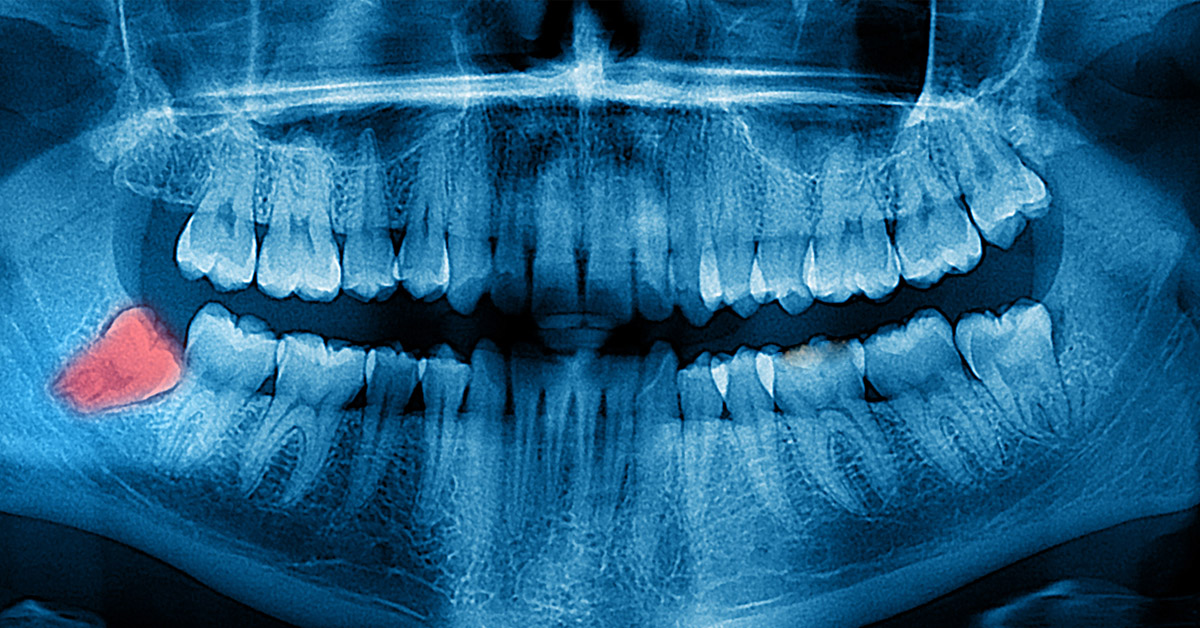

Todo empezó el 25 de mayo, cuando el joven solicitó que le extrajeran la muela que le incomodaba tanto. Cinco días más tarde, escribió en Zhihu (un foro chino de preguntas y respuestas) que su boca estaba “llena de sangre” y que llevaba varios días sangrando sin parar, además de que sangraba incluso dormido.

A la mañana siguiente, Liu regresó a la clínica dental para que le suturaran la herida de nuevo, sin embargo, no paró el sangrado. Su hermana cuenta que, el dentista estaba al tanto del problema e incluso fue él quien le recomendó regresar para suturarle la herida, pero realmente no parecía estar preocupado.